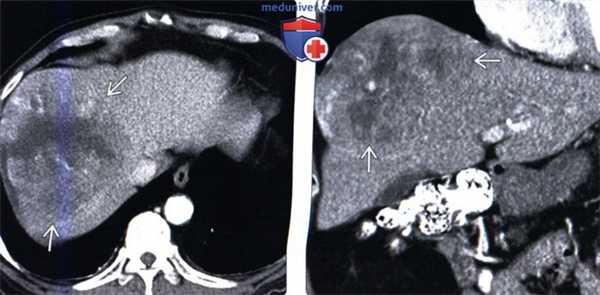

(Слева) На КТ в артериальной фазе контрастного усиления у мужчины 73 лет визуализируется большое, инкапсулированное объемное образование с участком некроза в центре и гиперваскулярной опухолевой тканью в периферических отделах. Изменения типичны для сарком в целом, хотя и не являются специфическими для первичной саркомы печени.

(Справа) На корональной КТ (реконструкция) у этого же пациента визуализируется большая саркома печени с центральным некрозом. При иммуногистохимическом исследовании не было обнаружено признаков мышечной, эпителиальной или сосудистой дифференцировки. Заключительный диагноз: недифференцированная саркома.

2. КТ признаки недифференцированной саркомы печени:

• Объемное образование большого размера, округлой формы, с наличием капсулы

• На периферии образования может обнаруживаться гиперваскулярная ткань жизнеспособной опухоли

• В опухоли часто имеются большие кистозные полости, участки кровоизлияния

• Могут обнаруживаться признаки инвазии кровеносных сосудов:

о Печеночных вен, воротной вены, нижней полой вены (НПВ)

• Опухоли большого размера, расположенные подкапсульно, могут разрываться

• Часто дает отдаленные метастазы и вызывает вторичное поражение лимфоузлов:

о Преимущественно в легкие и кости